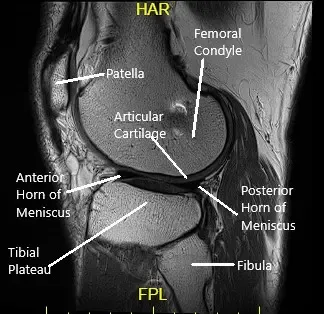

How the Body Part Normally Works? (Relevant Anatomy)

The knee joint is a hinge joint composed of the thigh bone (femur), shin bone (tibia), fibula, and kneecap (patella). The ligaments, cartilage, and menisci work together to provide stability and allow smooth movement.

- Articular cartilage cushions and protects the bones.

- Menisci serve as shock absorbers between the femur and tibia.

- Ligaments, including the ACL, PCL, MCL, and LCL, stabilize the knee by preventing excessive movement.

Ligaments

The ligaments of the knee along with the meniscus provide stability to the knee. Tears or rupture of the ligaments and menisci are the most common cause of knee buckling.

Anterior Cruciate Ligament (ACL)

The ACL runs from the front and middle of the tibia to the outer and backward side of the femur. The ligament provides stability mainly in the front and back of the knee. The ligament also stabilizes the rotatory movement of the knee.

Posterior Cruciate Ligament (PCL)

The PCL is present behind the knee joint. Along with ACL, it provides stability in the front and back of the knee. Similar to ACL, the PCL also provides rotational stability.

Medial & Lateral Collateral Ligaments

The medial collateral ligament provides stability on the inner side of the knee. Similarly, the lateral collateral ligament provides stability on the outer side of the knee.